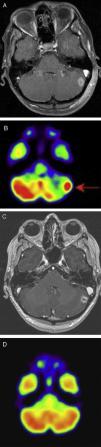

Mediante las imágenes biomédicas podemos diagnosticar, estadificar, controlar y valorar la efectividad de los procedimientos terapéuticos a los que son sometidos los pacientes oncológicos. RECIST (Response Evaluation Criteria In Solid Tumors) es el método para monitorizar el tratamiento mediante medidas unidimensionales de los tumores, obtenidas con técnicas de imagen reproducibles como son la TC, la RM y la PET. Los cambios metabólicos inducidos por los nuevos tratamientos modifican la biología y comportamiento del tumor, con discordancia ocasional entre el estado clínico del paciente y la respuesta medida con RECIST, lo que apunta a la necesidad de incluir pruebas funcionales en la valoración de la respuesta al tratamiento.

Biomedical imaging makes it possible not only to diagnose and stage cancer, but also to follow up patients and evaluate the response to treatment. RECIST (Response Evaluation Criteria In Solid Tumors) provides a method to monitor the response to treatment based on one dimensional measurements of tumors obtained with reproducible imaging techniques like CT, MRI, and PET. The metabolic changes induced by new treatments modify the biology and behavior of the tumor; occasionally, there is a discrepancy between the patient's clinical condition and the response measured by RECIST, which indicates that functional tests need to be included in the evaluation of the response to treatment.